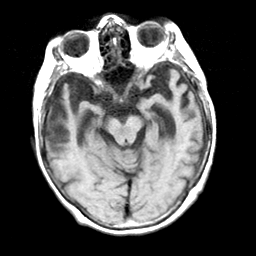

Pick's Disease, MR Study mr-t1 -- Slice #8

[Home][Help][Clinical] Slice 8